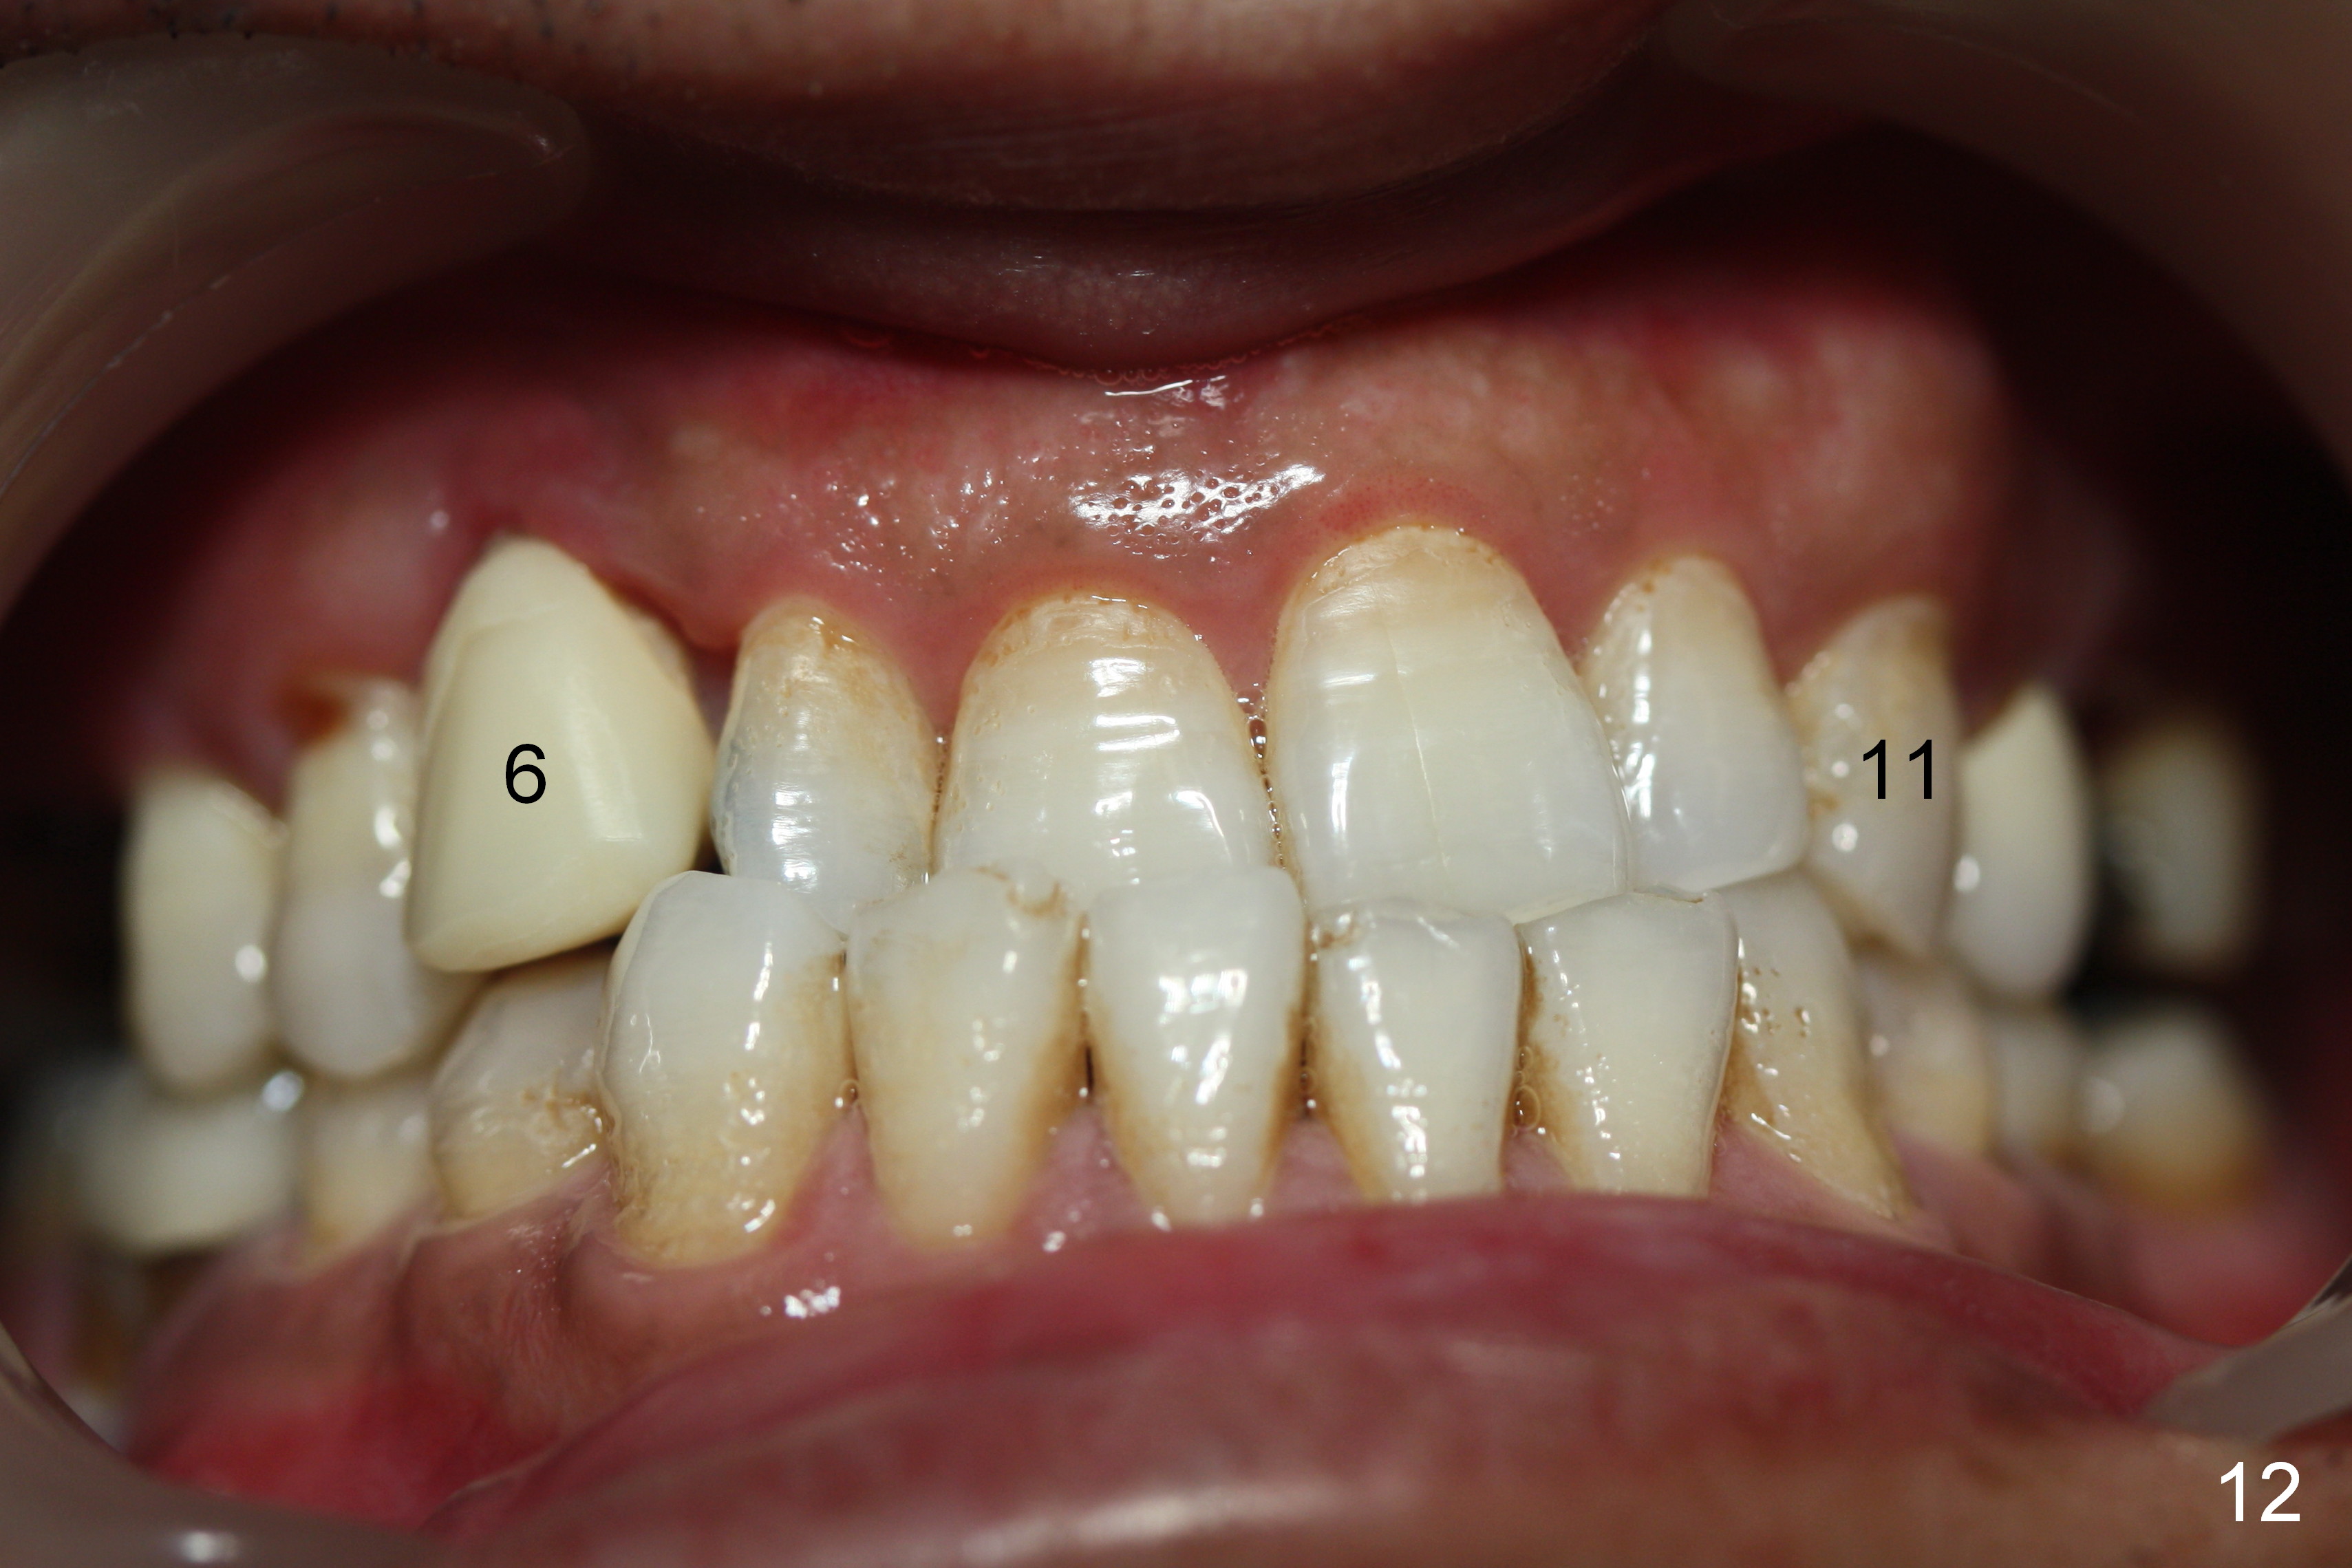

The patient returns 1.5 months postop. The provisional margin is much higher than that of the neighboring teeth (Fig.12,13: #6), unlike the opposite side (Fig.12: #11). When the provisional is removed, the implant margin is at the same level as that of the neighboring teeth (Fig.14 arrowheads). The implant margin is slightly extended apically (Fig.15 ^) prior to seating of the modified provisional. When the provisional is seated, its margin (Fig.16 ^) is at the implant margin; the gingival margin (*) is free and expected to move coronally by itself.